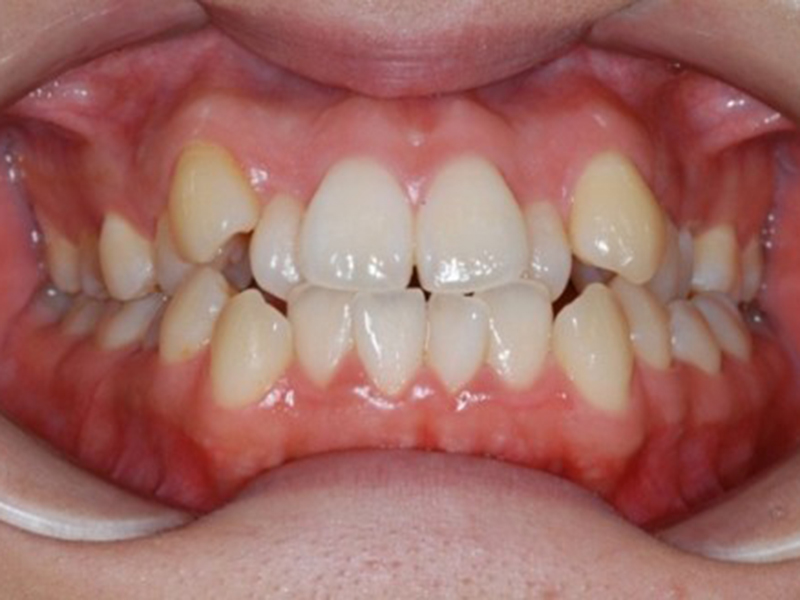

before